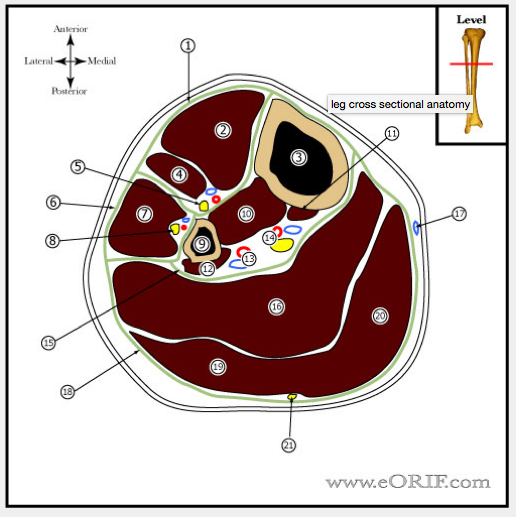

Name the following strucutres

1: anterior compartment

2: tib ant

3: tibia

4: EDL

5: deep peroneal & tibial vessels

6: lateral compartment

7: peroneus longus

8: superficial peroneal nerve

9: fibula

10: tib post

11: FDL (comes off tibia)

12: FHL (comes off fibula)

13: peroneal vessels

14: tibial nerve and posterior tibial vessels

15: deep posterior compartment

16: soleus

17: long saphenous vein

18: superficial posterior compartment

19: Lateral head of gastrocnemius

20: medial head of gastroc

21: sural nerve and lesser saphenous vein